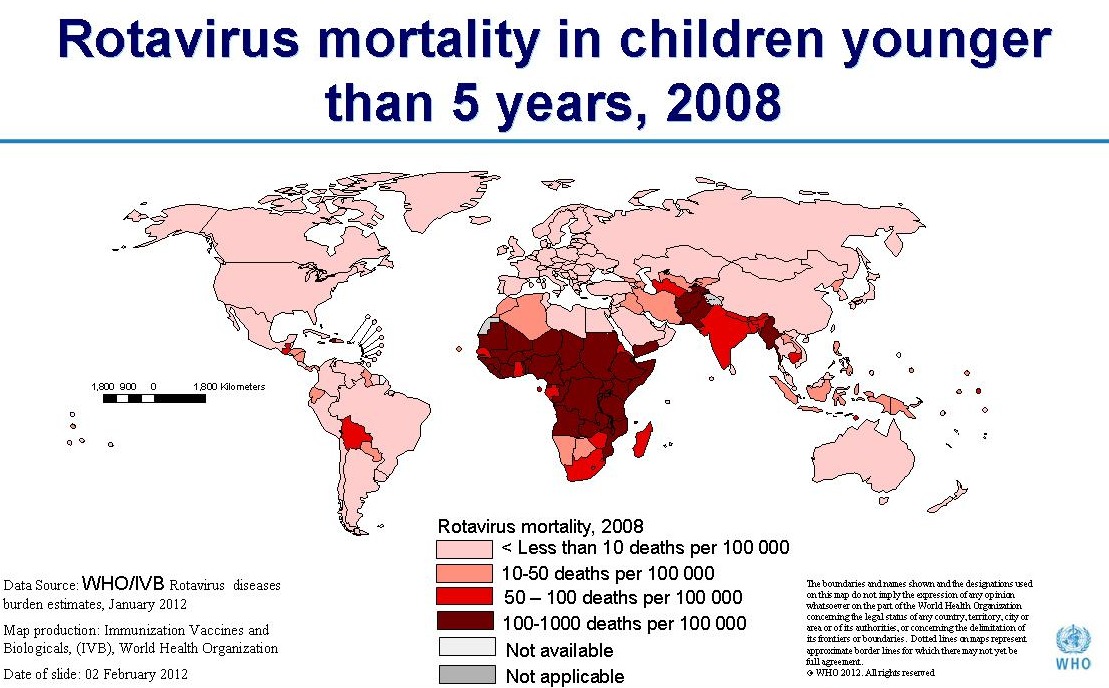

Rotavirus

Virus, fecal/oral transmission, contaminated water, food, surfaces

Virus, fecal/oral transmission, contaminated water, food, surfaces- Symptoms: diarrhea, vomiting,

- Complications: dehydration, sometimes severe resulting in cardiac arrest, sepsis, and death.

- Deaths/Statistics: before widespread vaccination, caused between 55,000 and 70,000 baby hospitalizations, and 20-60 deaths annually in the US.

- In 2008 worldwide, there were 453,000 deaths in children younger than 5 years of age due to rotavirus infections.

- As a virus, there is no treatment other than support through oral rehydration or IV fluids.

- Infants under 6 months of age are highly susceptible to rapid dehydration, and could be life threatening in hours.